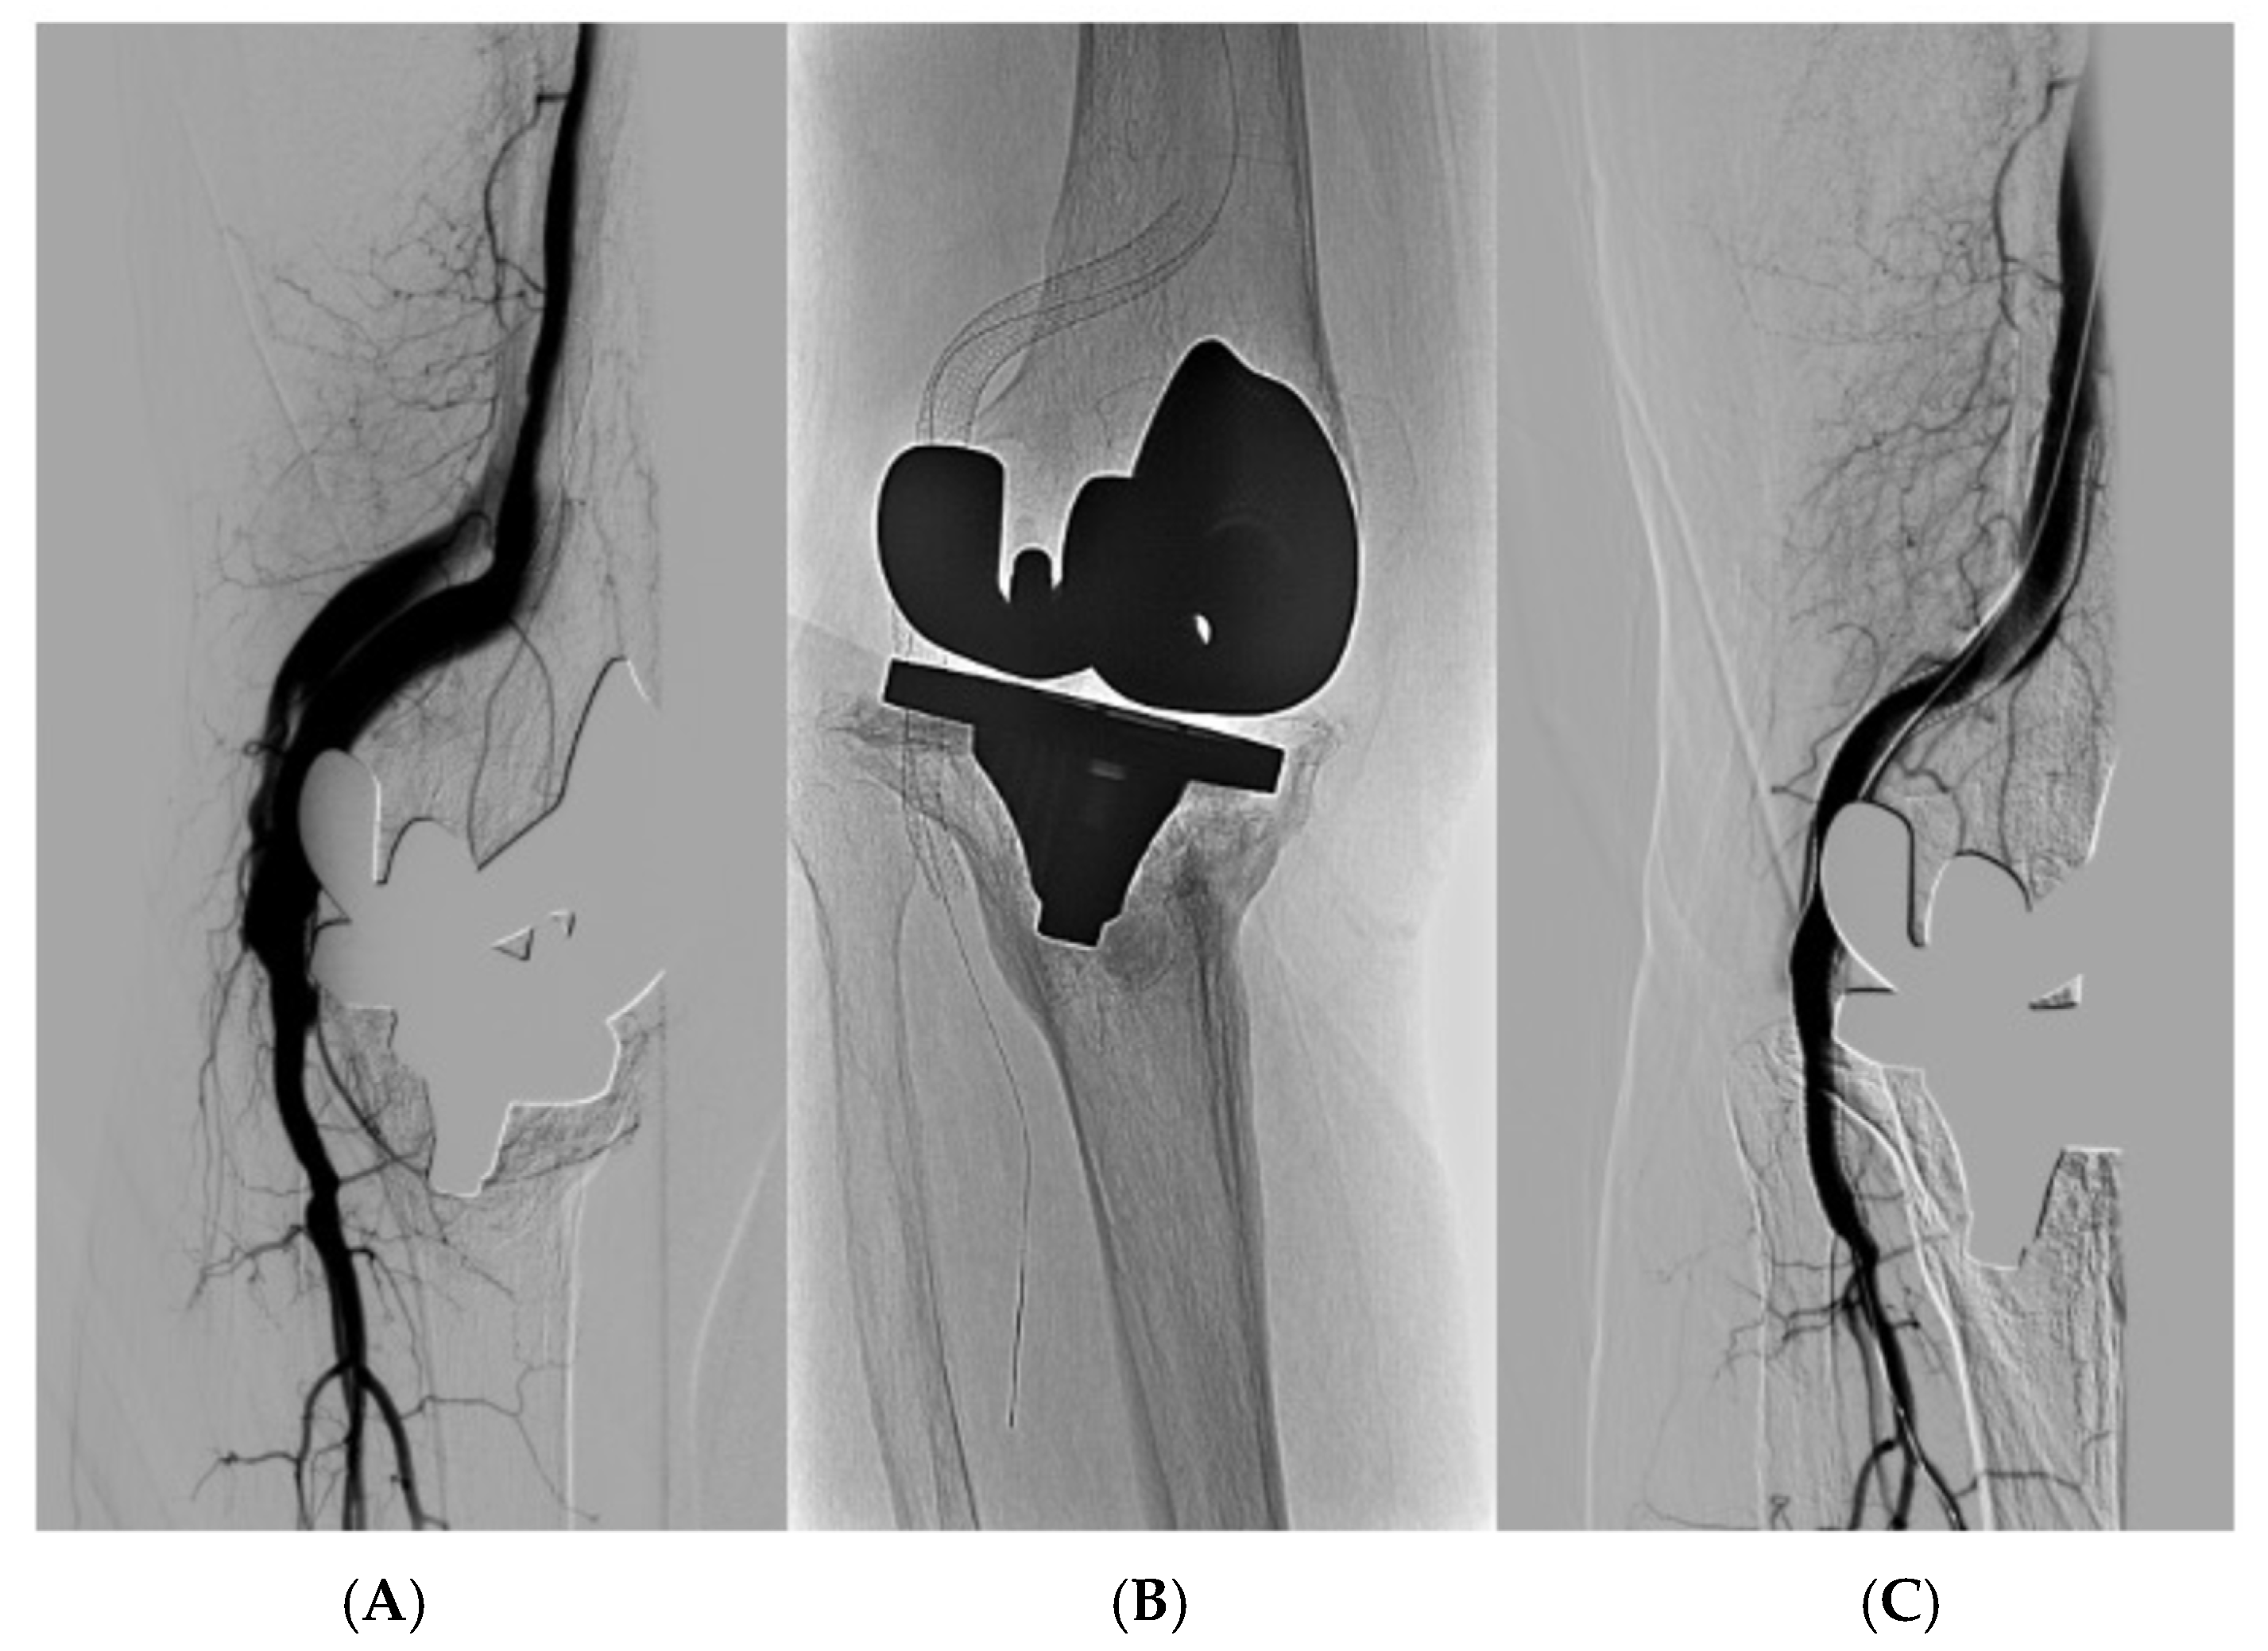

A physical examination finds a thrill (fremitus) and a murmur in the right knee. Palpable popliteal pulse, weak distal pulses. Iliotibial band (ITB) = 0.70. Normal lower left leg. The eco-Doppler reveals an arteriovenous fistula. An arteriography (Figure 1) confirms the presence of popliteal—popliteal arteriovenous fistula in the second portion, with a high flow.

Figure 1. Diagnostic arteriography. Early contrast packing of the surface femoral and popliteal veins.